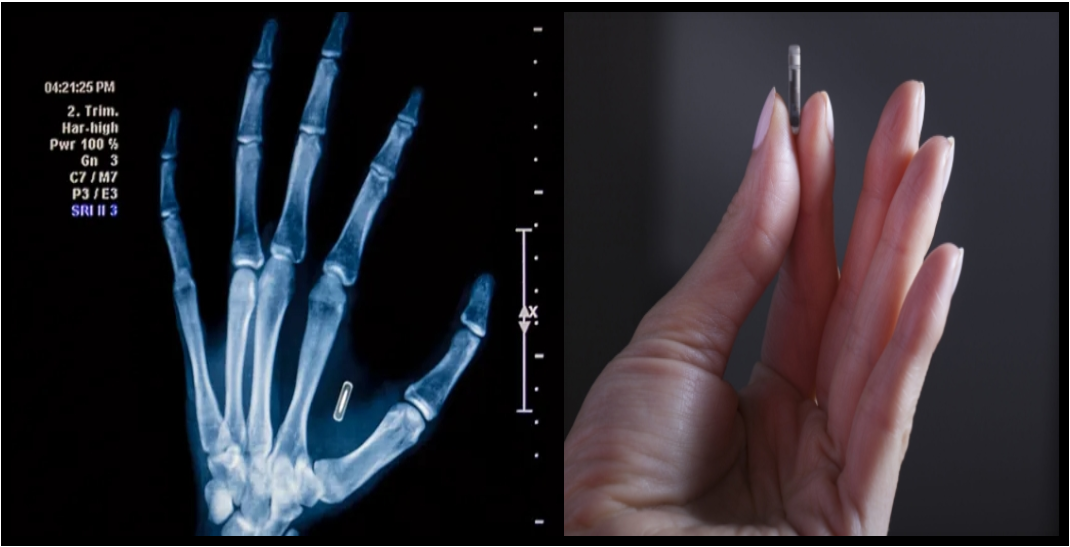

En Suède, une véritable révolution technologique est en marche : de plus en plus de citoyens choisissent volontairement de se faire implanter une puce électronique sous la peau, généralement entre le pouce et l’index. Ce petit dispositif, à peine plus grand qu’un grain de riz, contient une technologie NFC (Near Field Communication), la même que celle utilisée dans les cartes bancaires ou les téléphones pour les paiements sans contact.

L’initiative a vu le jour au milieu des années 2010, portée par des start-up comme Biohax International et Dsruptive Subdermals, qui ont vu dans cette innovation un moyen de simplifier le quotidien. En quelques années, plusieurs milliers de Suédois ont sauté le pas, souvent lors d’événements technologiques où les implants sont posés par des professionnels de santé en quelques secondes, sans anesthésie lourde.

En pratique, il suffit d’approcher la main d’un lecteur électronique pour que la puce transmette les données nécessaires.